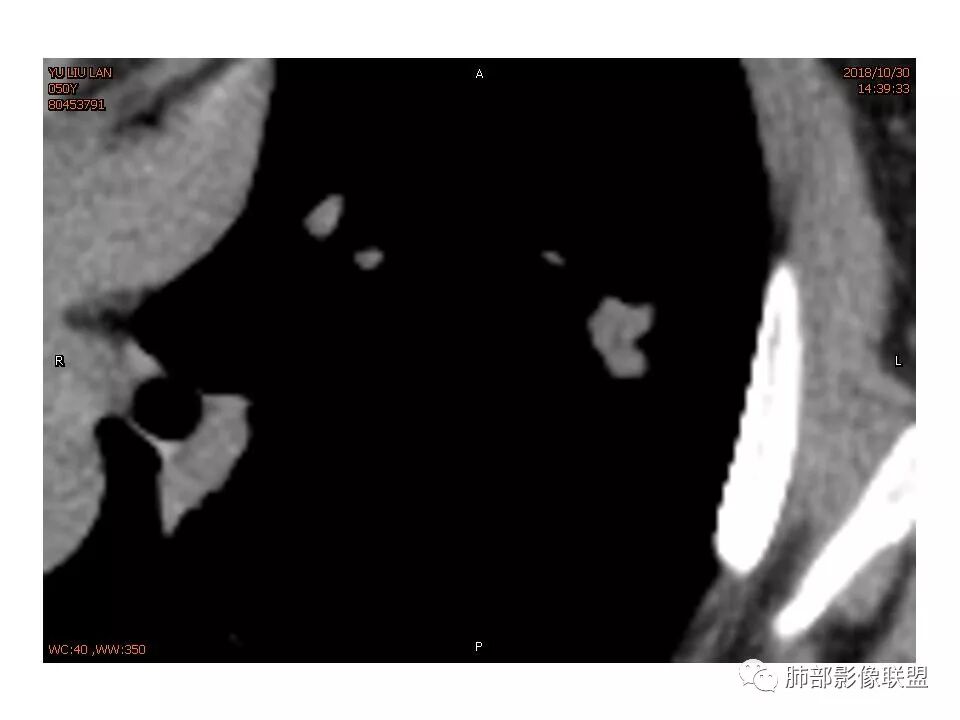

左肺上叶后段病灶,有毛刺,有胸膜牵拉,有血管滋养,好像还可以看见内部空泡,深分叶,边界比较清楚,考虑恶性肿瘤。

女,50。实性不规则结节,大小12*13mm,分叶、毛刺、胸膜凹陷,牵拉力强,增强渐进性强化,动脉期强化20,静脉期还有进一步强化。边缘强化,点状坏死。

其内血管被破坏。

左肺上叶实性不规则结节,有深分叶,短毛刺,有切迹,有血管集束,有胸膜牵拉,常规考虑恶性,鉴别炎性结节

女性,左上肺实性结节,有毛刺,有血管进入,边缘彭隆,月牙铲,深分叶,边界比较清楚,胸膜牵拉,考虑腺癌。

女性,50岁。U型凹陷、平直征

南边:支持炎性

1.胸膜下略不规则实性密度结节影,孤立,缺乏典型深分叶,可见淡薄边界模糊磨玻璃晕,可见相对细长软毛刺。

2.如南边老师分析,病灶缺乏边缘膨隆优势,甚至部分平直内收。

3.病灶收缩力不强,整体强化程度不显著。

4.综上,病灶更符合炎性,如隐球菌感染等,而不大符合肺腺癌。具体到机化性肺炎略有些出乎预料。